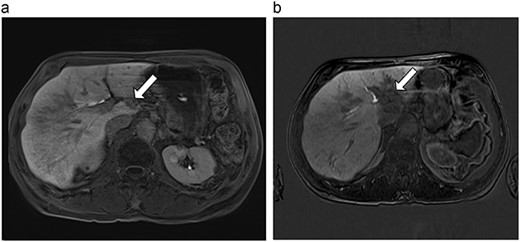

(a) Pre-ablation MRI demonstrates 6 mm lesion in caudate lobe of liver. (b) Post-ablation MRI (18 days postoperatively) demonstrates 40.4 mm complete ablation site in caudate lobe of liver.

| 1 (3a,b) | 61, F | Colon adenocarcinoma | 6-month FOLFOX | 1 | Laparoscopic microwave ablation | 6 | 40.4 | 34.4 | 10 | No |